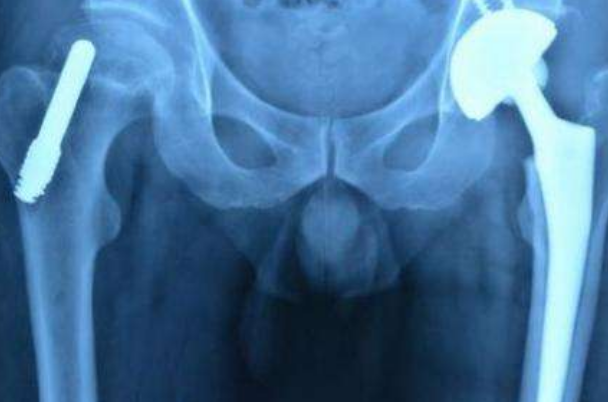

一般就是人工的股骨头置换手术,做完之后效果也是非常好的,需要养两三个月就可以了,患者就可以正常的走路,保持几年就要定期的去医院检查一下,看他的恢复情况,患者也可以根据物理的治疗,像是一些磁疗都会有缓解的症状,这些办法也特别适合病情不严重的人,不影响走路的人才可以这么做,这样才会有效果,如果特别严重的人对这种是没有效果的,所以要根据自己的情况来选择治疗方法。股骨头坏死也可以贴一些中药贴来缓解,可以用一些膏药,也有改善的效果。